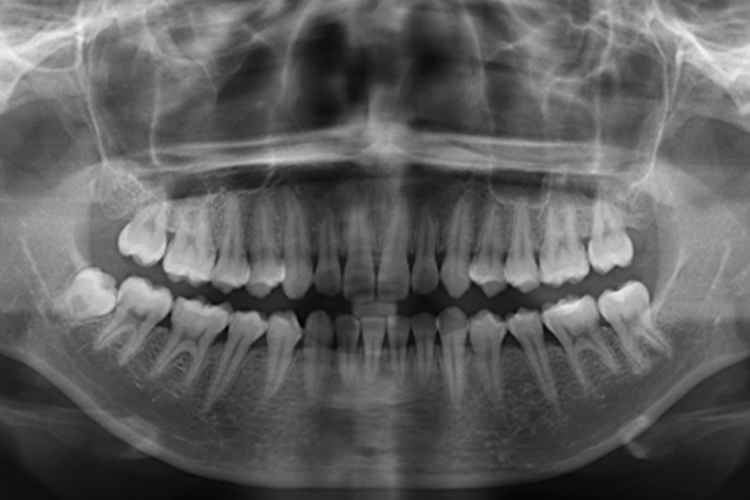

牙齿咬合指牙齿接触,牙齿咬合关系指咀嚼时牙齿接触关系,牙齿咬合关系分为正中咬合和非正中咬合,X光即X线片表现有所差异。

牙齿咬合关系分为正中咬合和非正中咬合,非正中咬合又分为前伸咬合及侧咬合,X线片表现有所差异。

下颌在正中位时,上下颌牙尖窝交错、最广泛地均匀接触。

前伸咬合:下颌前伸至上下前牙切端相对,然后滑回正中位过程中,前、后牙都有接触。

侧咬合:下颌侧方咬合至工作侧,上下颌后牙颊尖相对,然后滑回正中位过程中,工作侧牙尖相对接触。